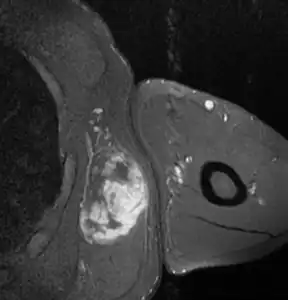

MRI of myxoid liposarcoma of high grade, in left axillary region of 40 year old man. Horizontal section.